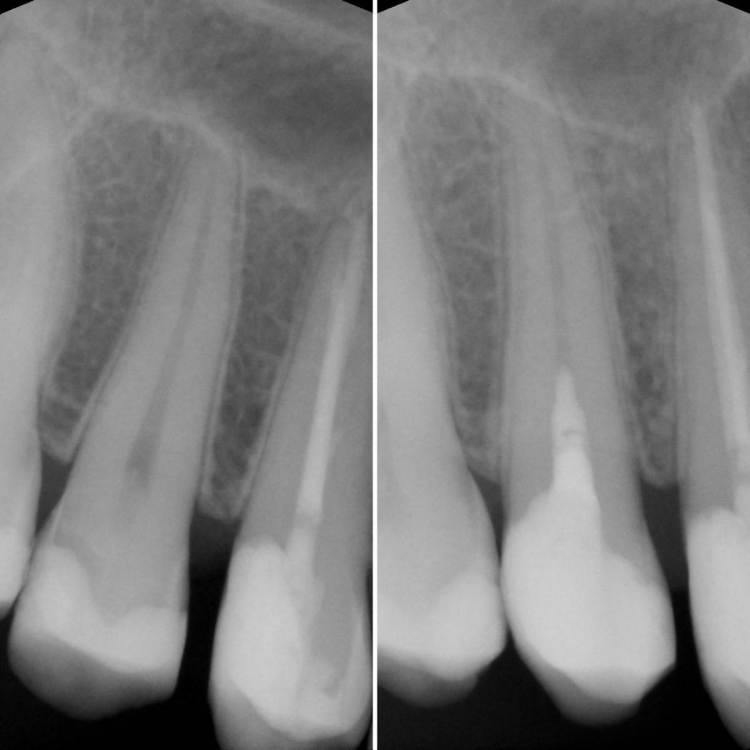

Гарриевич Опубликовано 3 мая, 2022 Поделиться Опубликовано 3 мая, 2022 (изменено) Хоть я и специализируюсь на эндодонтии, ну во главу угла всегда ставлю витальность зуба. В некоторых случаях проведение пульпэктомии не обязательно, А возможно ограничиться глубокой ампутацией пульпы. Изменено 3 мая, 2022 пользователем Гарриевич 3 Ссылка на комментарий

Гарриевич Опубликовано 3 мая, 2022 Автор Поделиться Опубликовано 3 мая, 2022 (изменено) Гемостаз и перекрытие мта гуттой Изменено 3 мая, 2022 пользователем Гарриевич 1 Ссылка на комментарий